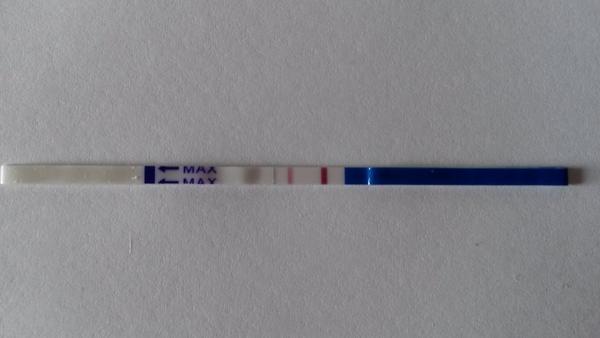

Chcela by som sa s vami podelit o moje testiky, v pondelok som davala foto mojho ´´dušíka´´ ktorý už vtedy nebol duchom, postupne silneli takto...avšak včera rano som sa zobudila na obrovsku bolest podbruska zbehla som na gyndu, kde hcg 115 na sone este nic, ale na lavom vajecniku utvar velkosti 4cm, mozne mimonaternicove tehitenstvo? s 3ma prizmurenymi ocami ma pustili domov s tym,ze v sobotu musim prist na dlasie hcg,ktore ak bude viac ako dvojnasobok sme v suchu...predpokladam ze ten utvar bola iba cysta a tie boli z jej prasknutia...teraz som uz fajn 🙂 a dnes som si spravila pre istotu dalsi test, a on silnie, takze myslim ze to MMT mozme vylucit 🙂 len pekne pozitivne! ale viac uvidime zajtra.